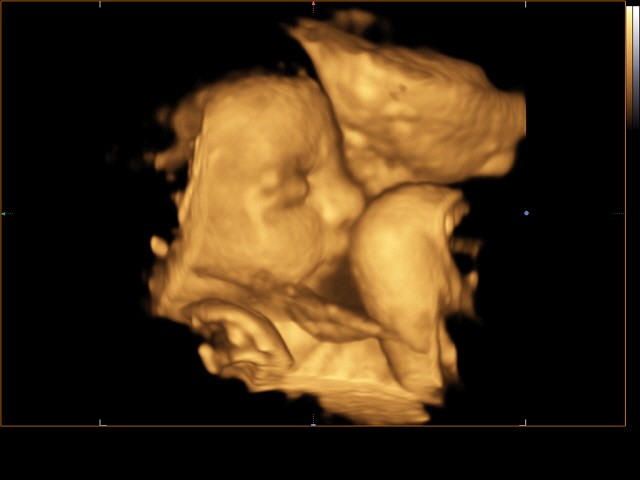

Ako jediný v okolí pracujeme s najmodernejším 4D ultrazvukovým prístrojom najvyššej triedy

Pre tehotné pacientky poskytujeme tehotenské poradne , prenatálny skríning a UZV diagnostiku na špičkovom UZV prístroji najvyššej triedy.